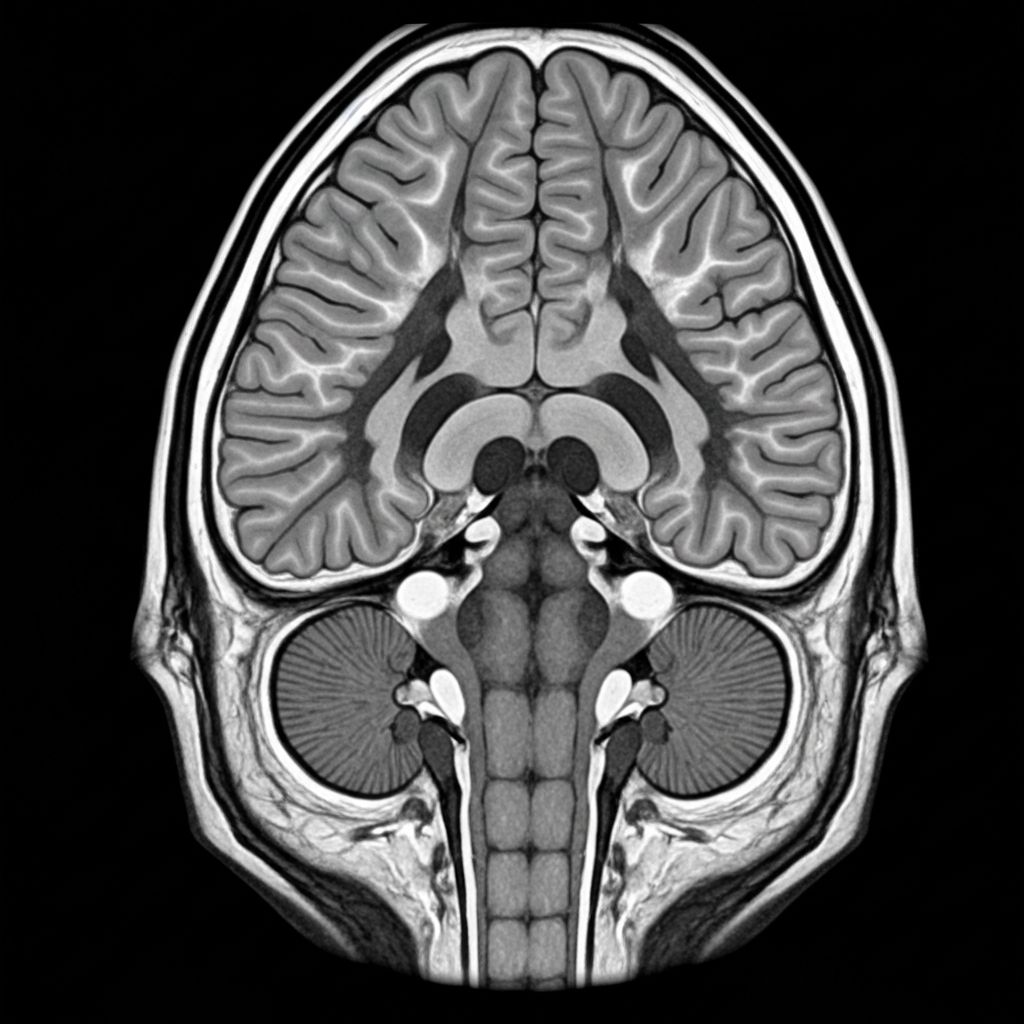

Die Aufmerksamkeitsdefizit-/Hyperaktivitätsstörung ist eine neurobiologische Erkrankung, die durch Veränderungen im Dopamin- und Noradrenalin-Stoffwechsel des Gehirns gekennzeichnet ist.

Bei ADHS liegt eine Störung im Dopamin- und Noradrenalin-System vor, die die Signalübertragung zwischen den Hirnregionen beeinträchtigt.